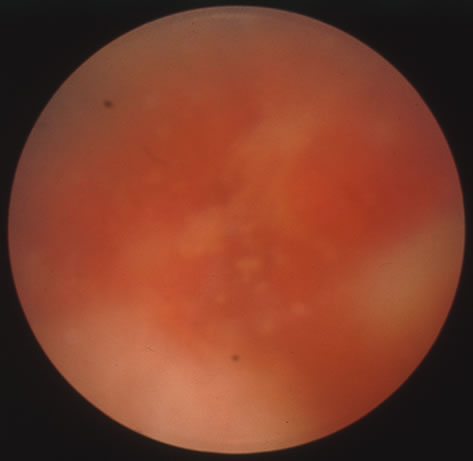

The acute retinal necrosis (ARN) syndrome is most often caused by the herpes zoster virus, although occasionally it may be a result of herpes simplex infection.12 It is typically described in healthy patients although association with immunosuppressed patients has also been described. Granular, nonhemorrhagic areas of retinal necrosis may be observed in the fundus, often rapidly coalescing with resulting blindness often caused by retinal detachment. There is often an associated vasculitis and vitritis. In immunocompromised patients VZV or HSV retinitis may also take the pattern of progressive outer retinal necrosis (PORN) (Fig. 6). PORN differs from ARN in that the former is multifocal, localized to the outer retina, and is less often associated with vasculitis and vitritis.